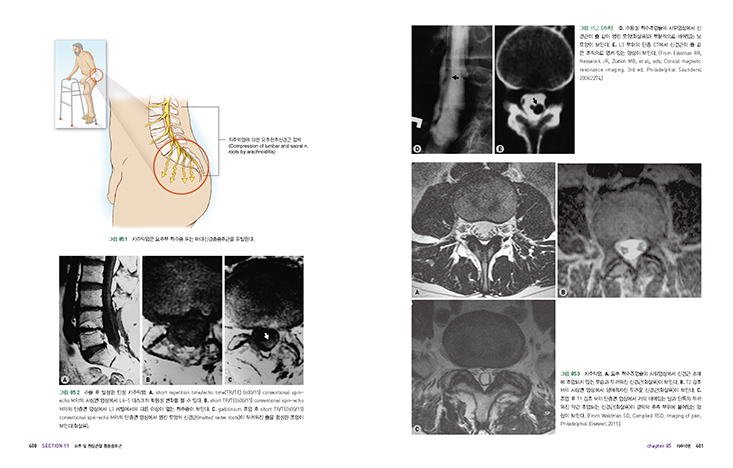

082 요추신경근병증

085 지주막염